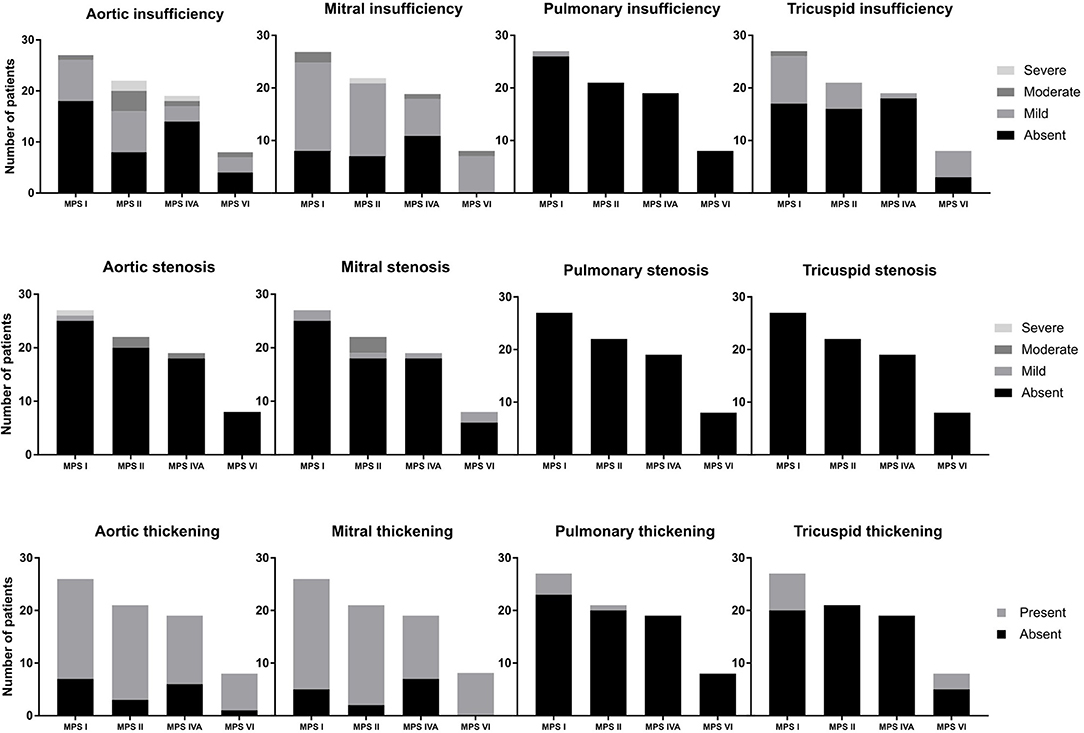

Valvular Disease

Among the 76 patients included in this study, left side valvular disease was a frequent finding, with mitral and aortic thickening being reported in most patients in all four MPS types (Figure 1). Furthermore, mitral and aortic insufficiency, mostly mild, were frequently found in patients with MPS I, II, and VI, but were also observed in a significant proportion of patients with MPS IVA. To a lesser extent, tricuspid valve thickening and insufficiency were also present in patients with MPS types I, II, and VI. Heart valve involvement was both more prevalent and more severe in adult patients (Figure 2; Table 3).

Figure 1. Prevalence of heart valve abnormalities in MPS types I, II, IVA, and VI, including both treated and untreated subjects.

For those 19 patients whose echocardiographic measurements were available before and after ERT start (11 children and 8 adults), a significant reduction of LVH parameters (including IVST, LVPWT, and LVM) was observed after ERT was started (Figures 3G–I), a finding that was not identified in 18 patients that remained untreated with ERT (Supplementary Figure 1). However, no statistically significant changes in SPAP, LAD, or LVEF were observed after ERT (Figures 3J–L). Moreover, ERT did not lead to significant improvements in valvular disease (Figure 5).

Figure 5. Comparison of valve abnormalities before and after ERT. In the statistical analysis, with Wilcoxon matched-pairs signed rank test, no significant difference was identified.

In this study, we assessed the prevalence of cardiac manifestations in a cohort of patients with MPS I, II, IVA, and VI; which included mostly patients treated with ERT. In agreement with previous reports (3, 17–20), valve involvement comprised mainly left-sided valves and affected a high proportion of patients. Mitral valve involvement was more common than the aortic valve in the four MPS types. Valve involvement, especially aortic insufficiency and mitral stenosis, was more commonly observed in older patients. We could not identify any significant worsening or improvement of valve pathology after ERT. It is widely accepted that ERT has limited impact on valve abnormalities of patients with MPS (13, 21–25), probably due to poor tissue penetration and irreversibility of the valvar damage. Nevertheless, it may have a role in preventing or delaying its appearance when treatment is started very early, as suggested by studies with sibling pairs and animal models (26, 27).